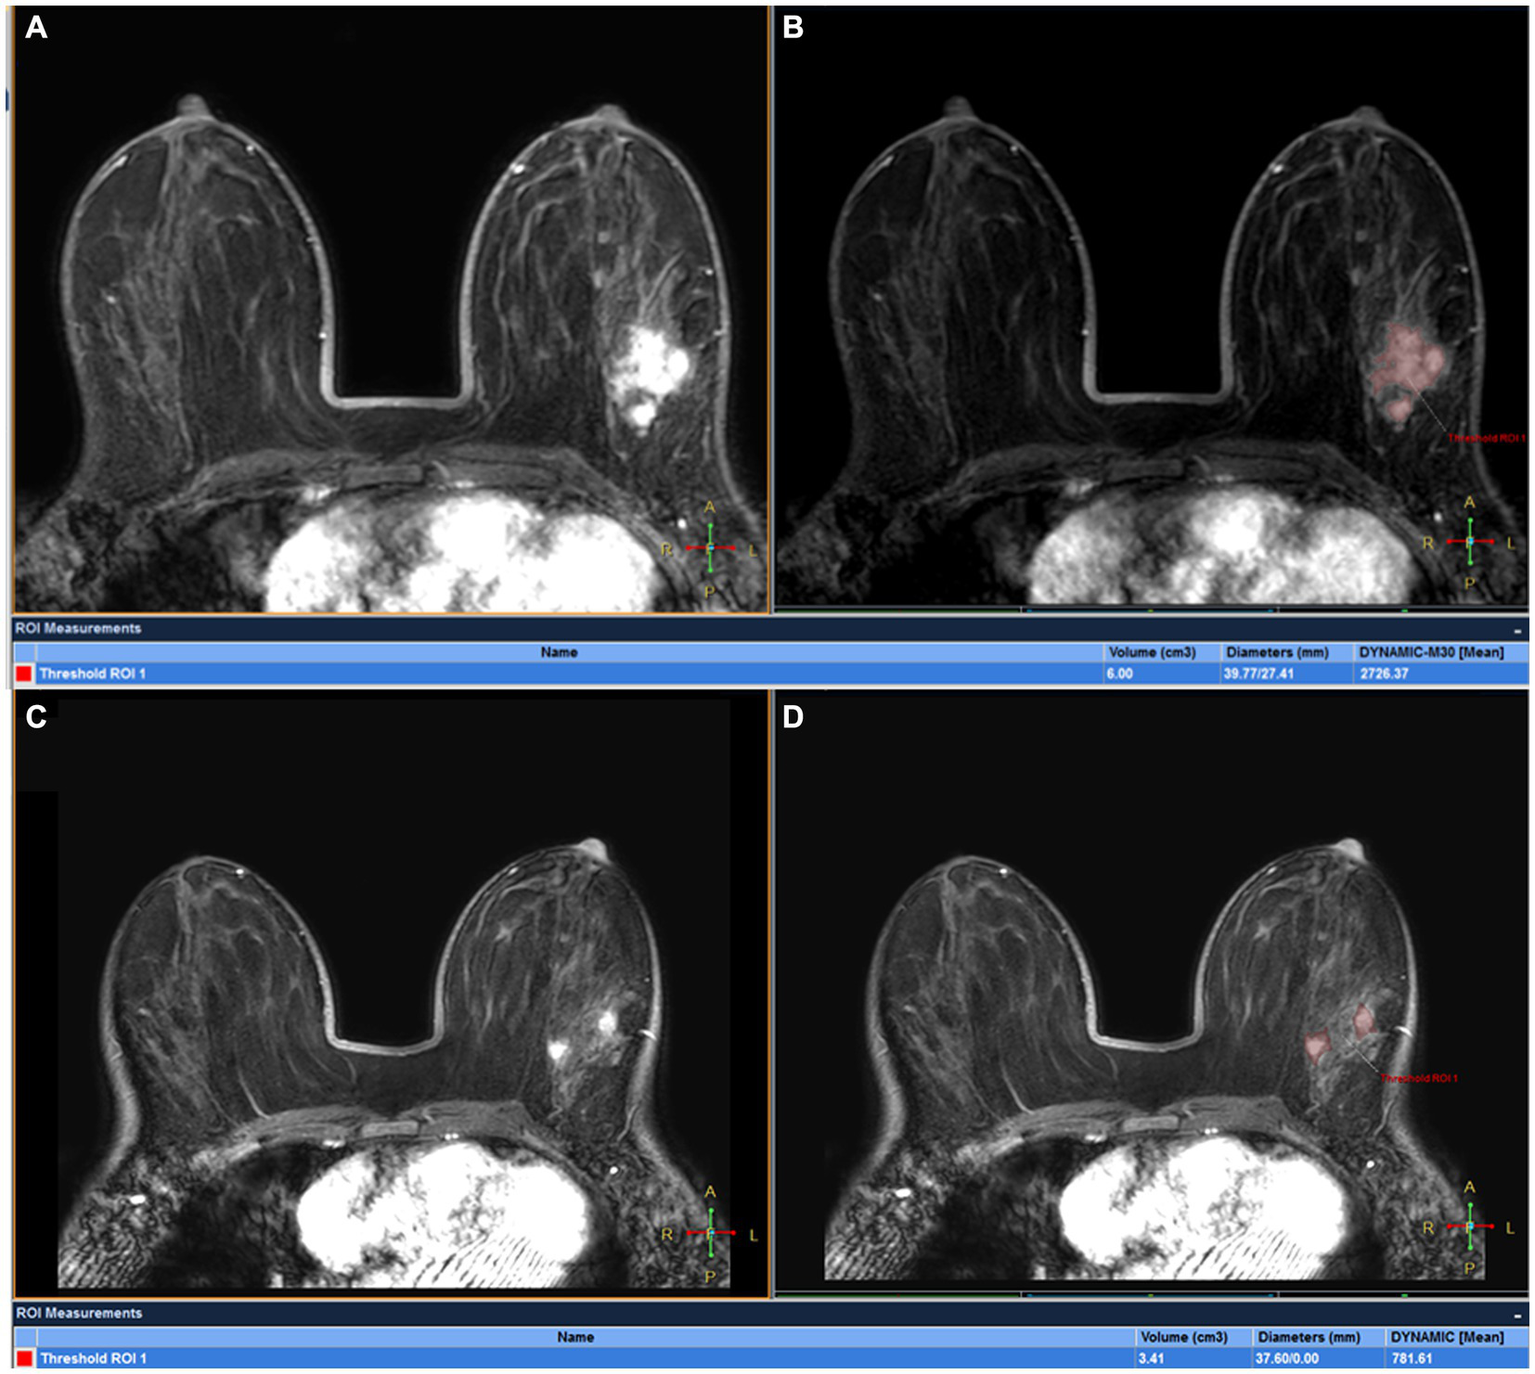

Figure 5

DCE-MRI of a 32-year-old woman with left ER+ invasive breast cancer at T0 (A,B) and T1 (C,D): tumor maxmium diameter meausred at T0 (Dmax0) and T1 (Dmax1) were 39.77 and 37.60 mm, respectively and tumor volume meausred at T0(V0) and T1(V1) were 6.00 cm3 and 3.41 cm3, respectively. The patient was confirmed by pathological analysis of the surgical specimen collected after first 2 cycles of NAC as having pCR.

Comparison of Dmax V, and ADC values between the two groups is also shown in Figure 5; Table 5. ∆Dmax values were significantly higher in MHR tumors compared with non-MHR tumors (p = 0.005). ADC0 and ADC1 values were significantly higher in MHR tumors than in non-MHR tumors (p = 0.038 and 0.035). There was no significant difference in Dmax0, Dmax1, V0, V1, ∆V, and ∆ADC between the two groups (p = 0.324).